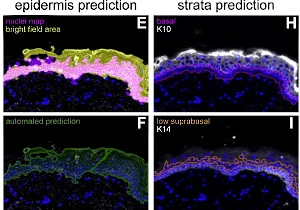

New StrataQuest App: IF ARTIFICIAL SKIN

The IF Artificial Skin App stratifies skin equivalents into dermis and epidermis, further dividing the epidermis into stratum corneum, suprabasal, and basal layers. It outputs area, mean staining intensity, nuclei counts, and % of marker-positive cells for each layer and sublayer. Read publication here